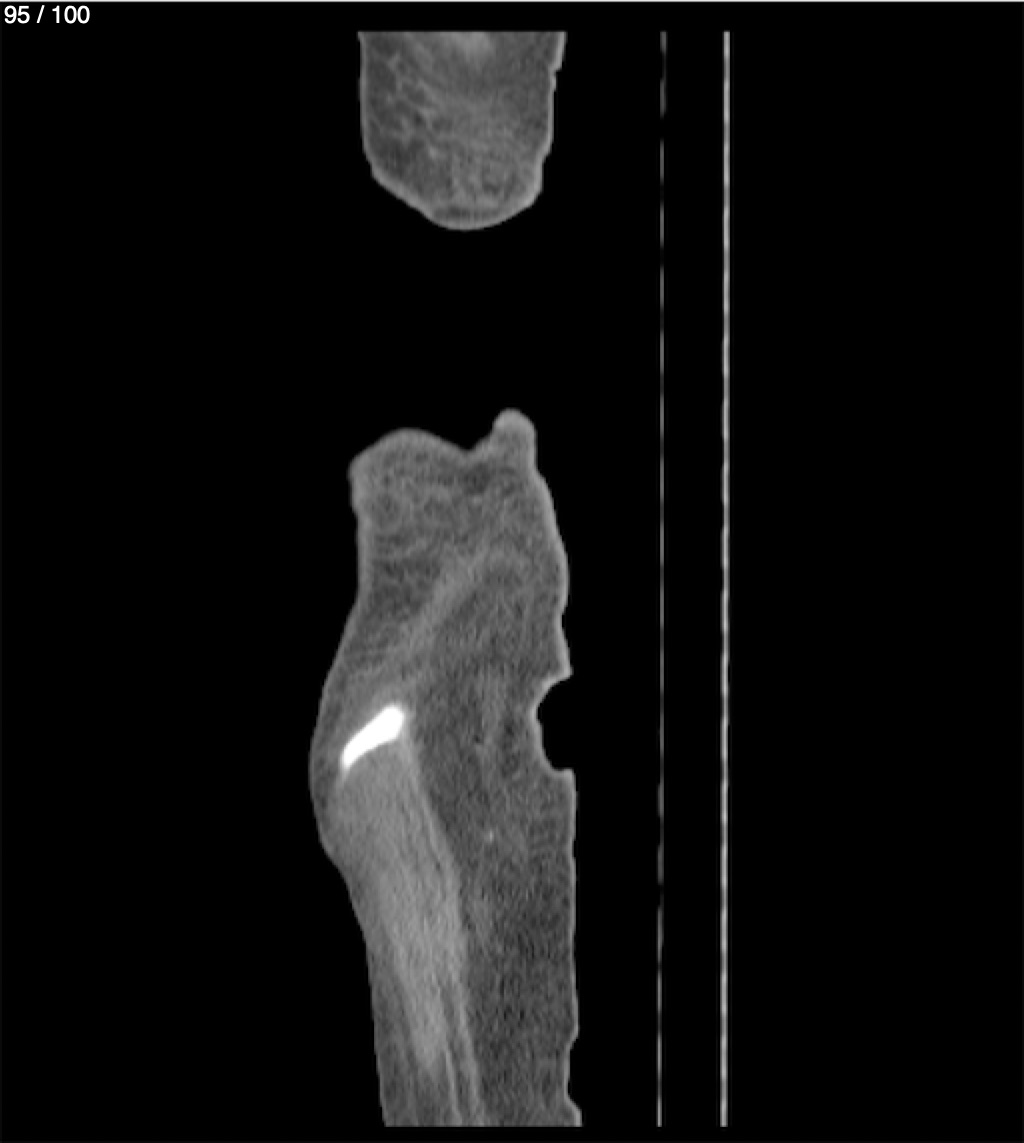

Hilda Geronimo Mendez 60A - T.C Abdomen Simple